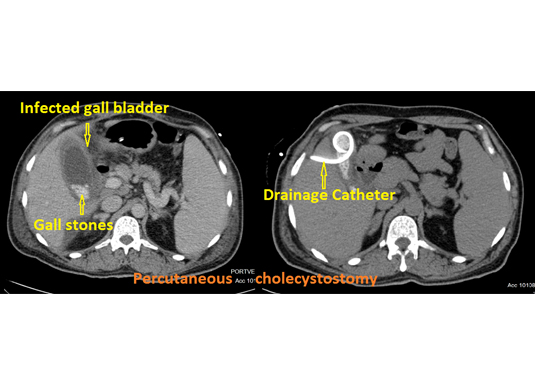

Acute cholecystitis is a condition where the outlet of the gall bladder is blocked by a stone and the gall bladder is infected. The treatment of choice is removal of the gall bladder (cholecystectomy) which is done under general anaesthesia. Patients whose general condition is not favorable for surgery can be treated by a procedure called percutaneous transhepatic cholecystostomy. In this procedure the contents of the gall bladder are drained outside by placing a catheter.

Few of the patients who have stones in their gall bladder get infected. Surgical removal of the gall bladder is the treatment of choice. Their general condition may deem them unfit for surgery and in these patients a procedure called percutaneous cholecystostomy. Here the infected bile in the gall bladder which is under pressure is drained outside by a plastic tube. Once the general condition of the patient improves this tube is removed and the definitive surgery is performed.